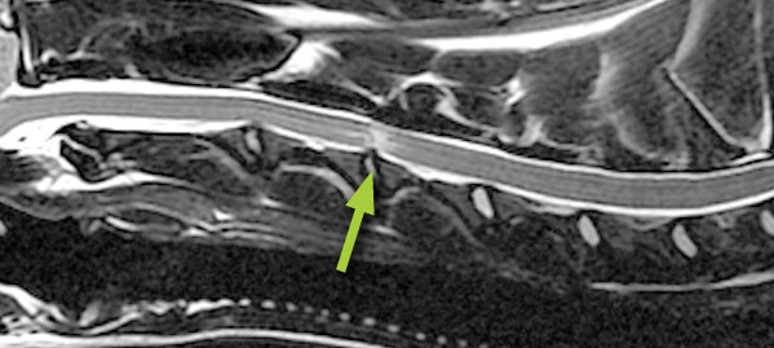

MRI with contrast media - slipped disc